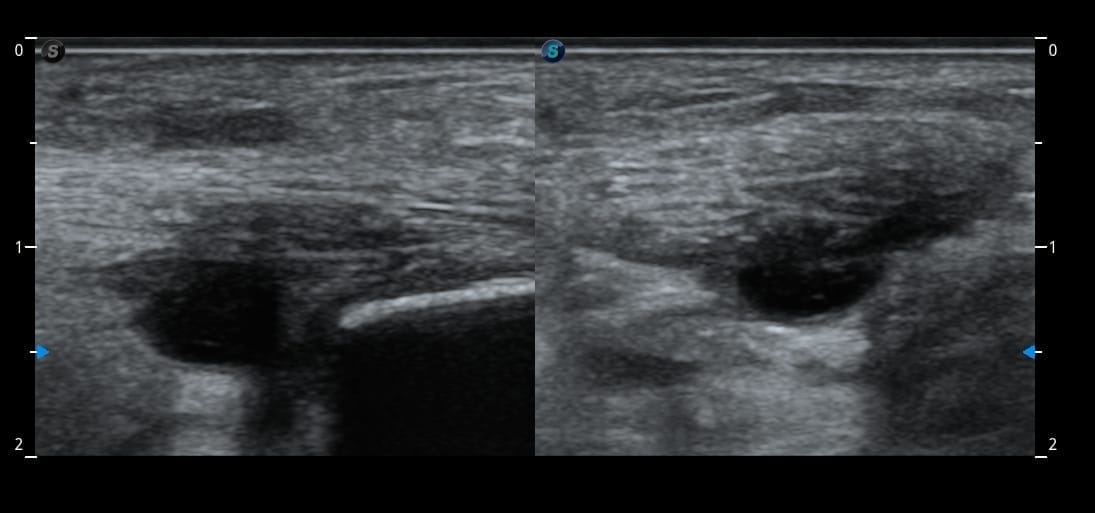

Une cheville en urgence

À l’examen, sa cheville est impossible à mobiliser tant elle est douloureuse. Elle m’explique que la douleur dure depuis plusieurs semaines, mais qu’elle n’a pas eu le temps de consulter en raison de la situation de son père.

Je décide donc de réaliser immédiatement une échographie musculo-squelettique en urgence de sa cheville, en parallèle de la gestion administrative de son père.

Résultat : des images surprenantes du tendon d’Achille chez une patiente jeune, qui font de ce cas une situation particulièrement intéressante à analyser.

Faites travailler votre œil et votre raisonnement avant la correction.

Quel est votre diagnostic ?

Analysez les images, repérez les éléments discriminants, puis confrontez votre hypothèse au raisonnement détaillé.